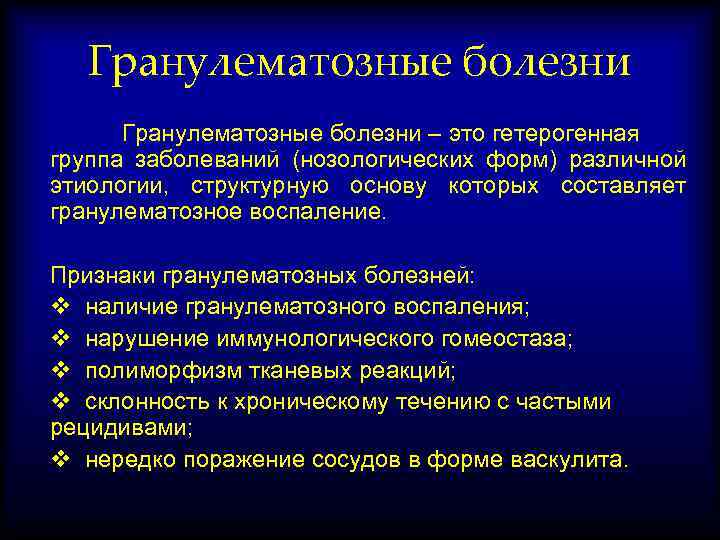

Справочник заболеваний: фотографии и иллюстрации